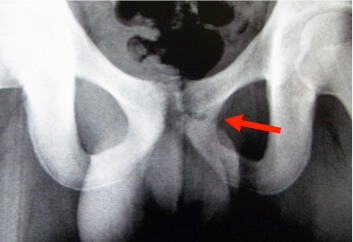

鑑別法としては股関節の内側(奥の方)が痛むときは骨格の歪みや老化による変形で軟骨がすり減っているか、股関節を包んでいる膜がはがれて関節に噛み込んでいることや血流が悪くなって壊死を起こしているケースが考えられます。

しかし夜寝ていても痛みがある場合はかなりの重症で、股関節に「のう胞」と言うできものがあるケースが多く、この「のう胞」が3つ以上ある場合は手術が第一選択になります。